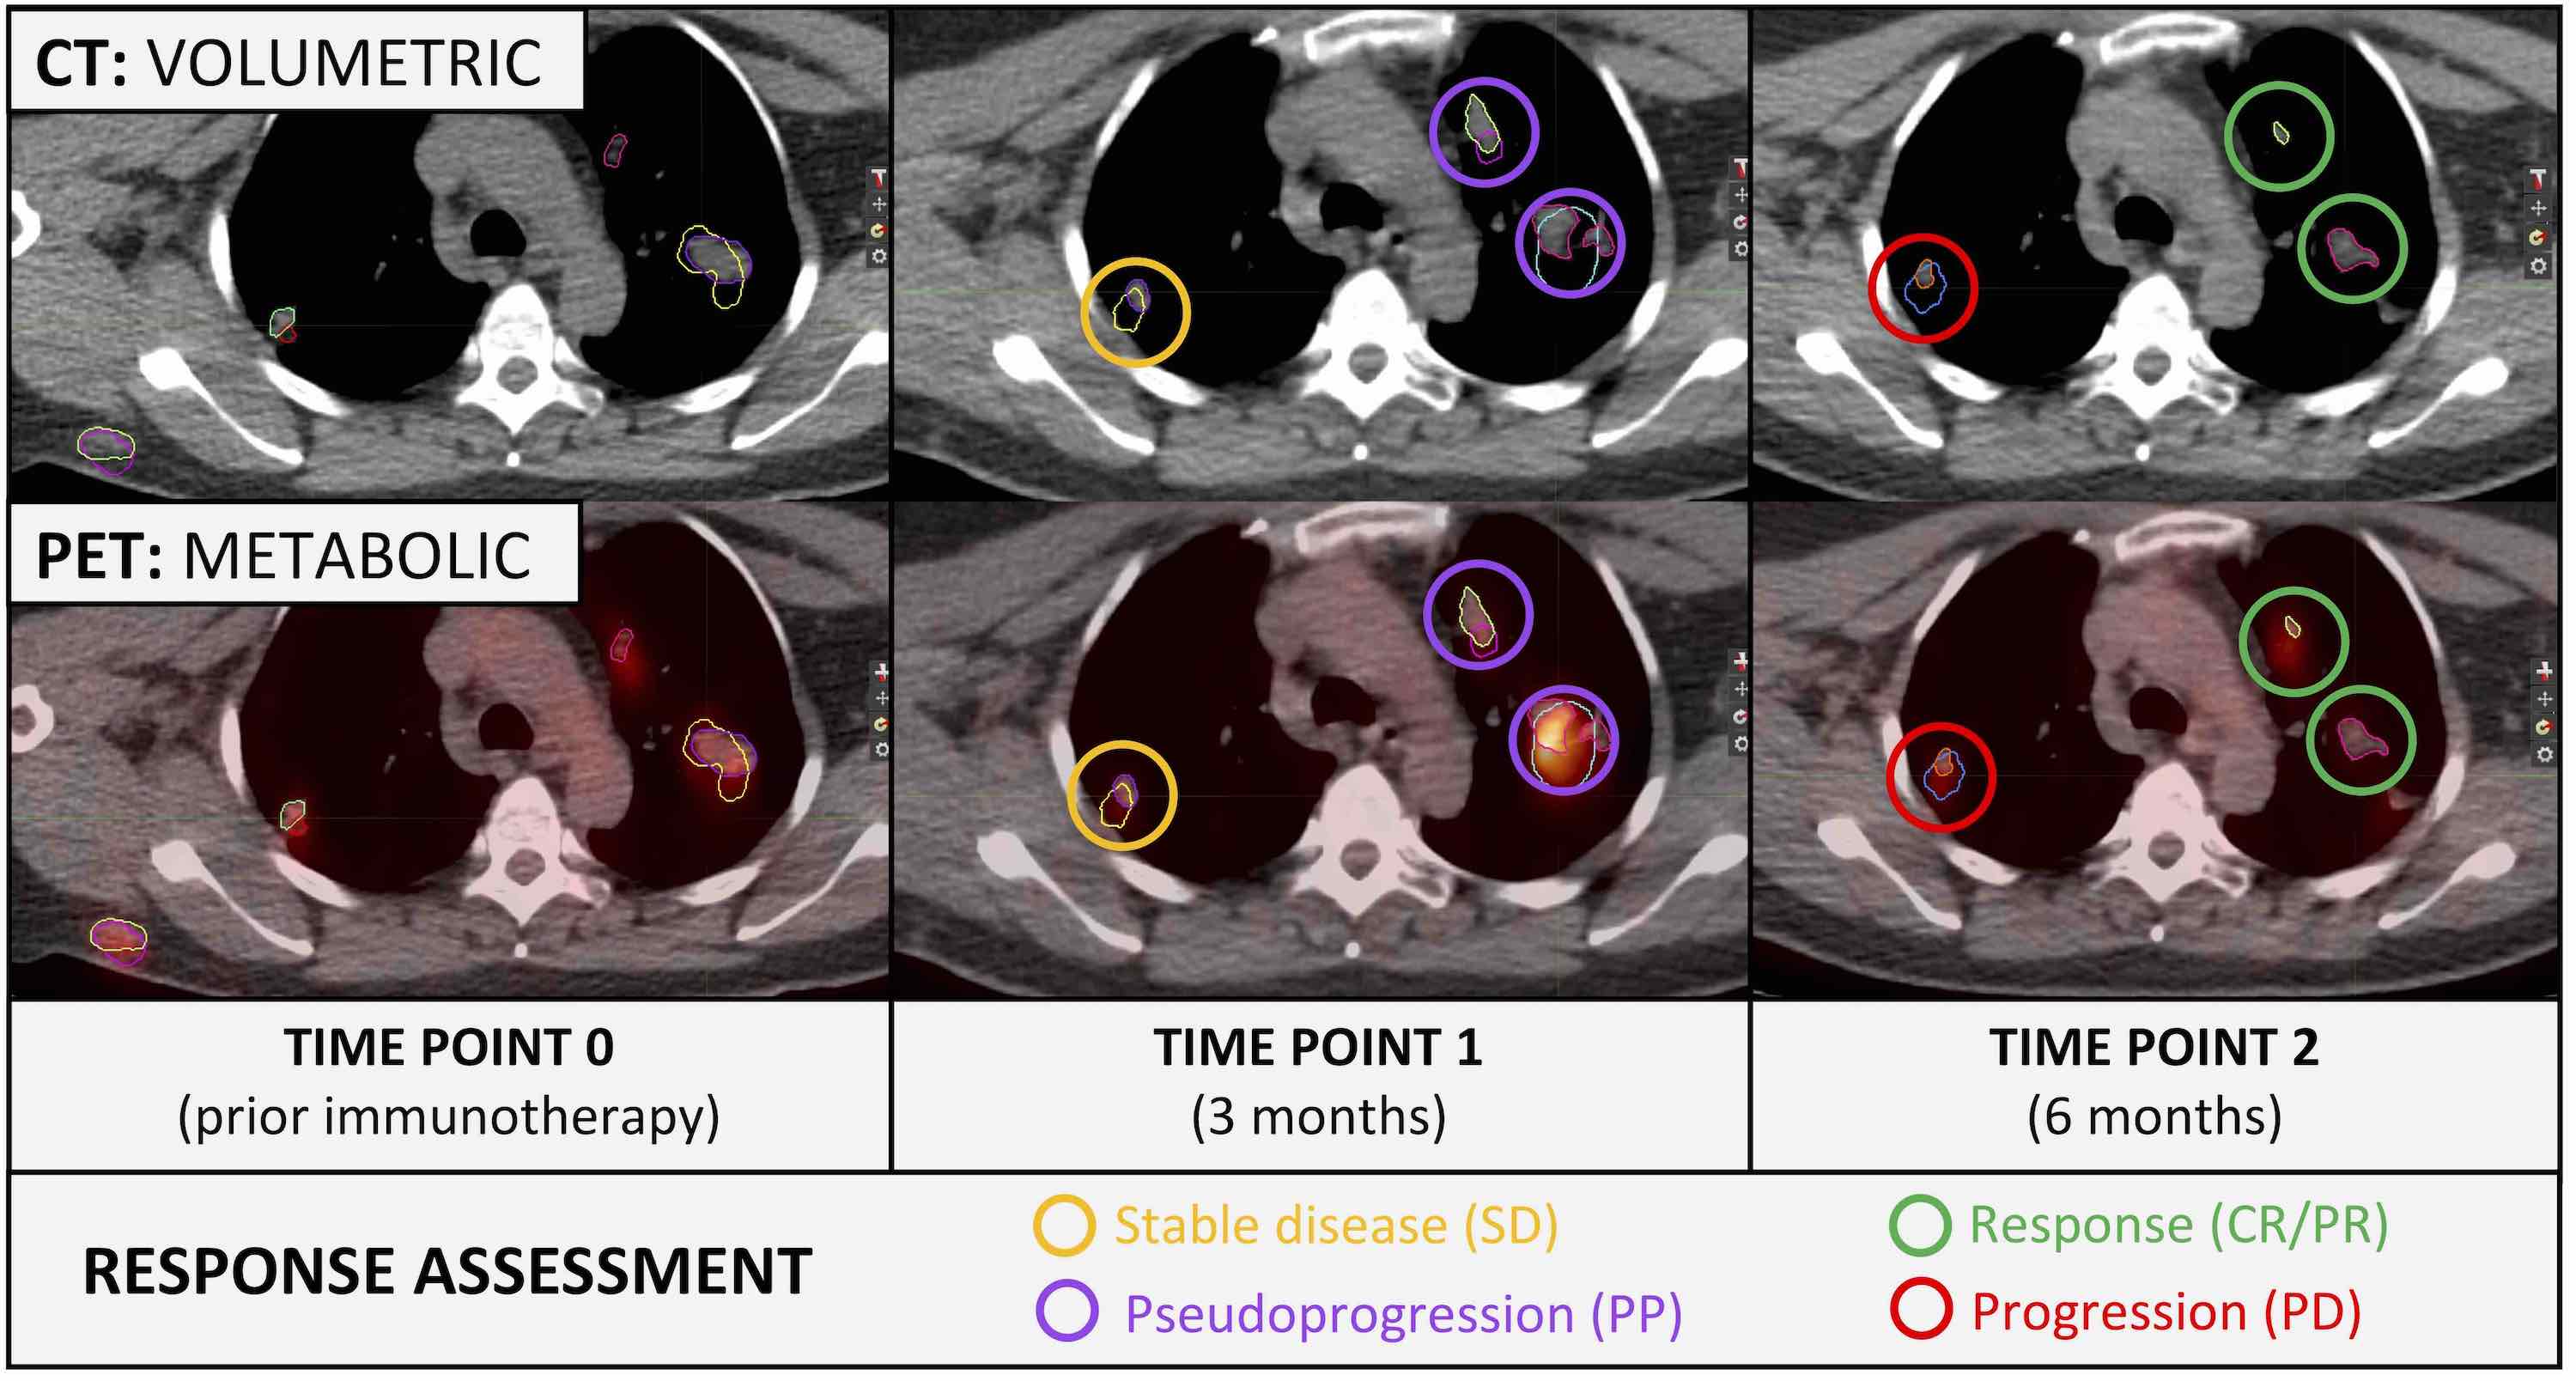

Radiomics, Tumor Volume, and Blood Biomarkers for Early Prediction of Pseudoprogression in Patients with Metastatic Melanoma Treated with Immune Checkpoint Inhibition

Immune checkpoint inhibitors (ICI) have revolutionized the treatment of patients with metastatic melanoma. However, more than 50% of patients do not respond to ICI. ICI response assessment is challenging, as novel response patterns, such as pseudoprogression (PP) are not considered in the response evaluation criteria in solid tumors (RECIST 1.1).

An increase in tumor volume could be based on either true progressive disease (TPD) or on influx of immune-competent cells (PP). Early differentiation of PP and TPD is highly relevant in daily clinical decision-making, and predictive biomarkers are needed for better patient selection. We could identify 2[18F]fluoro-2-deoxy-D-glucose–positron emission tomography/CT-based radiomic and delta-radiomic features as novel imaging markers for early differentiation of PP from TPD. In addition, we could show that the routine blood markers LDH and S100 can contribute to PP prediction.

A multimodality approach of combined radiomics and blood marker–based prediction model at an early time-point of 3 months yielded the best performance. Thereby, added toxicity or delayed treatment switch in patients with metastatic melanoma treated with ICI might be potentially avoided.